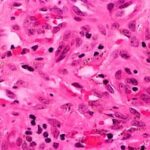

The variable epidermis may be hyperkeratotic with focal parakeratosis, acanthotic to atrophic, and with focal spongiosis. There is proliferation of small blood vessels in the papillary dermis, forming lobular aggregates {glomeruloid proliferation}. The proliferation may be florid, mimicking Kaposi’s sarcoma {acroangiodermatitis} . There is a superficial perivascular lymphocytic infiltrate that surrounds thickened capillaries and venules. The reticular dermis is often fibrotic. Extravasated erythrocytes and hemosiderin are usually present superficially, but they may be identified about the deep vascular plexus as well. Fibrin thrombi may be observed in the small vessels, likely reflecting flow disruption and anoxia. They do not indicate a concurrent coagulopathy. Endothelial necrosis and neutrophils may be present as well, reflecting similar changes, and do not indicate a leukocytoclastic vasculitis